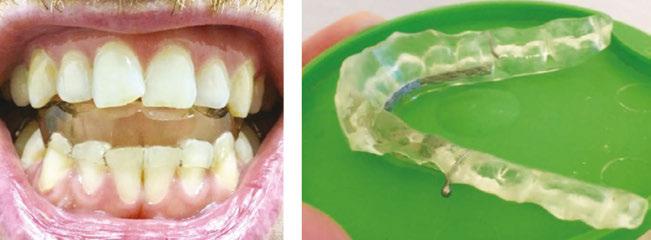

tan was referred to my office by a TMD specialist. His chief complaints were he could not chew or open his mouth without pain. It seemed the less he chewed, the more pain he experienced. As a result, an Orofacial Myofunctional Therapy (OMT) program was created to help support his muscles of the TMJ and craniofacial respiratory complex. He used his splint as instructed by his specialist. However, his anterior open bite widened, and his teeth became more misaligned over time.

Stan was a 28-year-old male in a lot of pain. He had just come from his TMJ specialist where he received an oral orthotic splint to relieve his discomfort. He told me it all started after a long dental appointment where he received a root canal and a new crown on the upper right. After this procedure, his jaws felt tight so he gave it a good stretch by opening very wide. He heard a rip and a crunch. Opening his mouth was never the same after that. He presented with a set of symptoms: TMD muscle pain, he could no longer chew his food without pain (food had to be the soft consistency of tofu), daytime clenching and night time grinding of his teeth. In addition, he had daily headaches and ear ringing. He could not open his mouth very wide without experiencing sharp pain. He took acetaminophen for his discomfort and zolpidem nightly to help him fall asleep easier.

Upon closer examination, there were contributing factors that led to his discomfort. Stan had been a stomach/face sleeper for years. He also bit his nails since childhood, had a smoking habit from his youth, and he was prone to ear infections. He had moderate tongue and buccal ties, obligate mouth breathing, aggravated by a deviated septum, narrow nares, low tongue resting posture, an

anterior open bite, a lower jaw that deviated upon opening, and bouts of acid reflux.

An orofacial therapy program was created to allow his tongue to give better support and function to his oral structures, especially the TMJ joint. When the tongue naturally rests in the palate, it removes the unwanted pressure off of the TMJ. As part of the course of his therapy, focus was made to reeducate his breathing to make his nose the primary way he breathes. Optimal breathing rate for an adult is slower than for a child. Good nasal breathing during the day supports good nasal breathing during the night for optimal sleep. When the tongue rests in the palate, it impacts facial development especially for children who are still growing. An adult, for example, like our friend Stan, the progress made is gradual but more likely to last a lifetime. Generally, therapy starts out once a week for about 2-3 months. Then therapy progresses to every other week for 2-3 months, and then changes to once a month for about 5 months for the rest of the year. The exercises are done a minimum of 2 times everyday. These exercises are designed to strengthen and tone the orofacial muscles, building brand new neuromuscular function. When the muscles of the face are well developed, it may favorably impact appearance and the overall integrity of the facial structures. The muscles of the face also include the tongue, lips, cheeks and neck. Although the therapy program is typically only a year, Stan really liked how good he felt and decided to continue with some of the exercises to this day. From the photos you can see how much the program has impacted his health and well-being.

During his therapy, there was a discussion about the possible benefits he may receive from having his jaws expanded, making more room for his tongue, then to be followed by a tongue and buccal frenums release. His intermolar width is 34 mm, and his intercanine width is 25 mm. I feel any expansion has a potential benefit.

After completing his course of myofunctional therapy, he was able to open his jaws with full range of motion and achieve his goal of being able to enjoy some of his favorite foods again. He was most excited about being able to bite into a juicy cheeseburger.

To document any initial assessment, the midpoint of therapy, and when therapy has ended, it is important to take detailed photos, videos, plus full measurements of the face and teeth. This makes it possible to compare results while showing that your therapy works based on the evidence you gathered before, during, and after treatment.